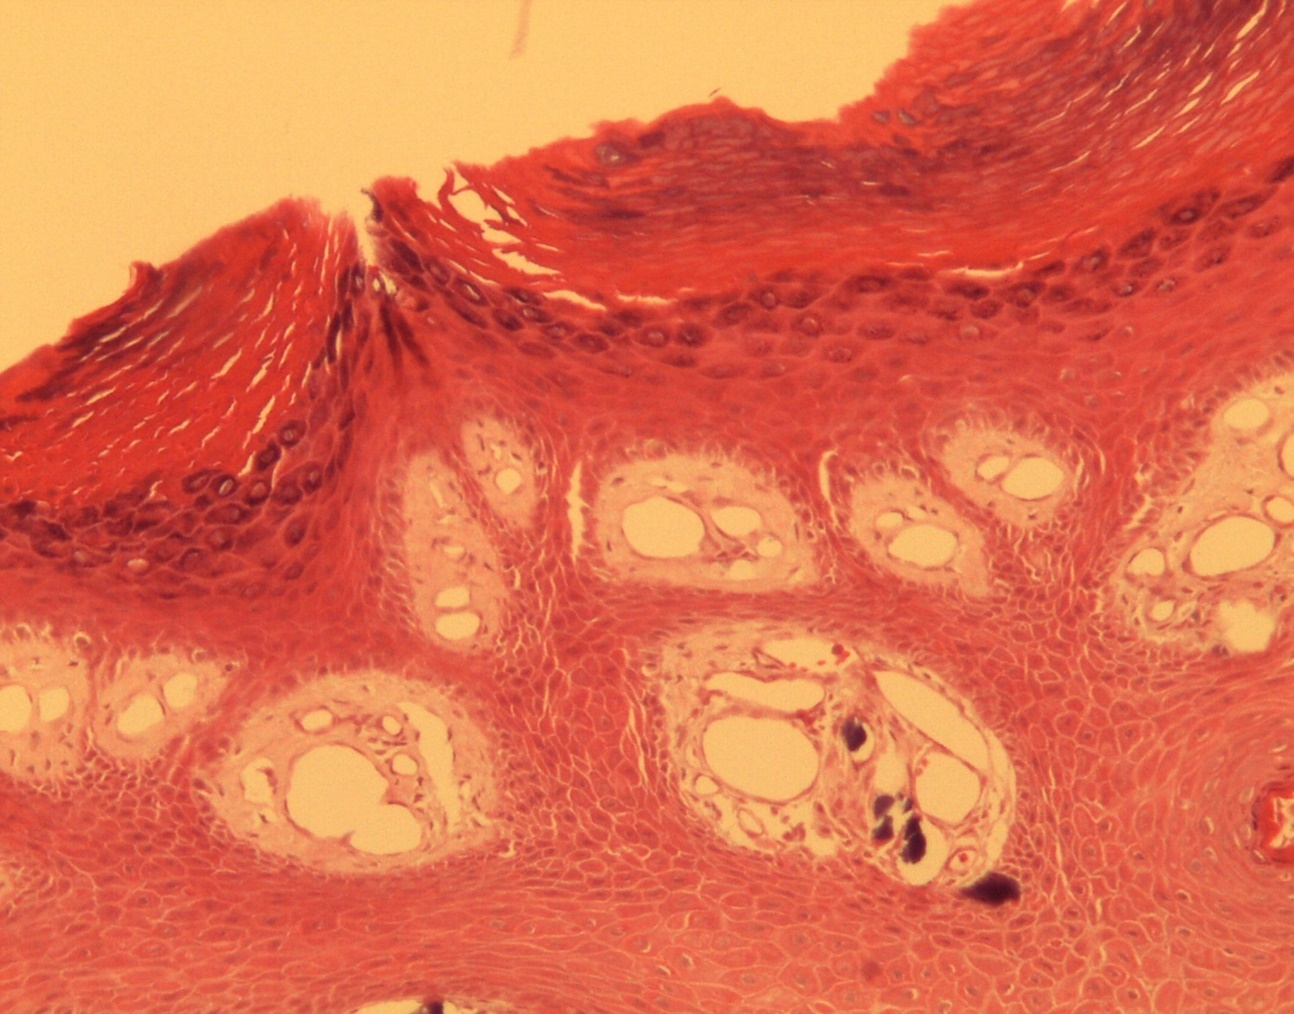

A 9-year-old male patient who was treated in the dermatology service for a progressively growing keratotic nummular dermal lesion on the right knee. With the clinical judgment of viral wart, the lesion was removed. In the Pathology Service, a nummular keratotic lesion of 0.5 cm in maximum dimensions was received, which crackled when cut. Figure 1, Figure 2, Figure 3, Figure 4, Figure 5

Figure 3.Relationship of calcium foci in the papillary dermis with the overlying epidermal hyperplasia. HE. 200x.

Relationship of calcium foci in the papillary dermis with the overlying epidermal hyperplasia. HE. 200x.